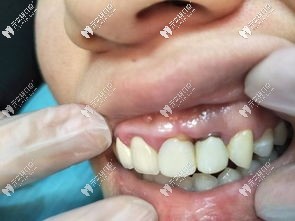

齲壞的上門牙

▲4顆齲壞的上門牙

起初只是上門牙長蛀牙有兩三年,平常吃東西總是塞牙,還經常發(fā)炎疼痛,但她一直拖著沒處理;后來導致齲洞越來越大,牙神經壞死,并在牙根尖處形成慢性炎癥,時間一長,根尖的慢性炎癥就病變成了根尖囊腫,導致局部牙槽骨吸收,在頜骨內形成內含囊液的空腔。